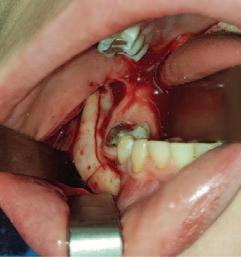

2. Wright, J.T., Crall, J.J., Fontana, M., Gillette, E.J., Nový, B.B., Dhar, V., et al Evidencebased clinical practice guideline for the use of pit-and-fissure sealants: a report of the American Dental Association and the American Academy of Pediatric Dentistry. J Am Dent Assoc 2016; 147 (8): 672-682.e12.

3. Lygidakis, N.A., Garot, E., Somani, C., Taylor, G.D., Rouas, P., Wong, F.S.L. Best clinical practice guidance for clinicians dealing with children presenting with molar-incisorhypomineralisation (MIH): an updated European Academy of Paediatric Dentistry policy document. Eur Arch Paediatr Dent 2022; 23 (1): 3-21.

4. Frencken, J.E. The state-of-the-art of ART sealants. Dent Update 2014; 41 (2): 119-120, 122-124.

CLINICAL TIPS

FIGURE 2: Effective cotton wool roll isolation. FIGURE 3: Conditioning of the pits and fissures. FIGURE 4a: Application of a GI sealant (GC Fuji IX). FIGURE 4b: Manipulation into the pits and fissures using the ‘finger press’ technique.

30 Journal of the Irish Dental Association | February/March 2023: Vol 69 (1)

FIGURE 5: GI fissure sealant.

A sagittal split osteotomy approach for removal of a large cementoblastoma at the mandibular angle

Précis

This case report demonstrates the effectiveness of sagittal split osteotomy in the removal of a mandibular cementoblastoma.

Abstract

Benign lesions at the angle of the mandible are frequently removed by a conventional intra-oral approach to gain access and achieve complete visualisation. This method is quick and effective when dealing with small, benign lesions that are superficially located at the angle of the mandible. The removal of large and deeply located lesions with a conventional intra-oral approach, however, brings about a unique set of challenges, particularly when the third molar is displaced towards the inferior border of the mandible, including: lack of complete visualisation of the lesion; difficulty in identification and protection of the inferior alveolar nerve; and, the necessity of removing a considerable amount of osseous structure, thus increasing the risk of a mandibular fracture. Alternative techniques for such lesions include an extra-oral approach, but this could potentially create a cosmetic defect from cutaneous scarring and can result in facial nerve injury.

This case report describes the use of a unilateral sagittal split osteotomy (SSO) in the removal of a mandibular cementoblastoma. This is a safe and effective technique allowing optimal access to the tumour with complete visualisation, identification and protection of the inferior alveolar nerve, and with minimal bone removal, while maintaining mandibular integrity, strength and facial aesthetics.

Introduction

A cementoblastoma, also referred to as a true cementoma, is a rare, benign odontogenic tumour arising from ectomesenchymal cells.1 They have also been referred to in the literature as: sclerosing cementoma; peri-apical fibroosteoma; and, peri-apical fibrous dysplasia. Disorganised proliferation of cementoblasts results in subsequent deposition of cement-like tissue around the roots of teeth. Cementoblastomas account for between 0.69% and 8% of all odontogenic tumours and tend to occur between the second and third decades of life, with a median age of 20 years and an age range of eight to 44 years. Some studies show no gender preference,2 while others show a higher rate of occurrence in males.3 Cementoblastomas tend to occur more frequently in the posterior mandible, involving the roots of premolar and

molar teeth. They are asymptomatic lesions, which demonstrate a slow and expansile growth, and are usually discovered as an incidental radiographic finding.4 However, cortical bone expansion can result in facial asymmetry and symptomatic painful lesions when facial nerves become involved.5 Because cementoblastomas have unlimited growth potential, treatment includes tumour resection with the extraction of the associated tooth. If the tumour is small at the time of diagnosis, treatment may consist of surgical removal with endodontic therapy and retention of the involved tooth. The traditional surgical approach for excision of a cementoblastoma at the mandibular angle is removal of bone to gain access to the tumour. However, the surgical risk increases with removal of larger lesions via traditional techniques, which will involve the removal of larger amounts of bone,

PEER-REVIEWED

Journal of the Irish Dental Association February/March 2023; 69 (1): 31-35

BA APsych BDS NUI MFD RCSI MB BCh BAO Surgical SHO

BDS

FFDRCSI

Registrar in Oral and Maxillofacial Surgery South Infirmary Victoria University Hospital Cork

FDS

in Oral and Maxillofacial Surgery South Infirmary Victoria University Hospital Cork Corresponding author: Dr Mar Cotter. E: mcottdentist@gmail.com Journal of the Irish Dental Association | February/March 2023: Vol 69 (1) 31

Dr Mar Cotter

Mr Zeeshan G. Khattak

MSc OMFS MFDS RCPS